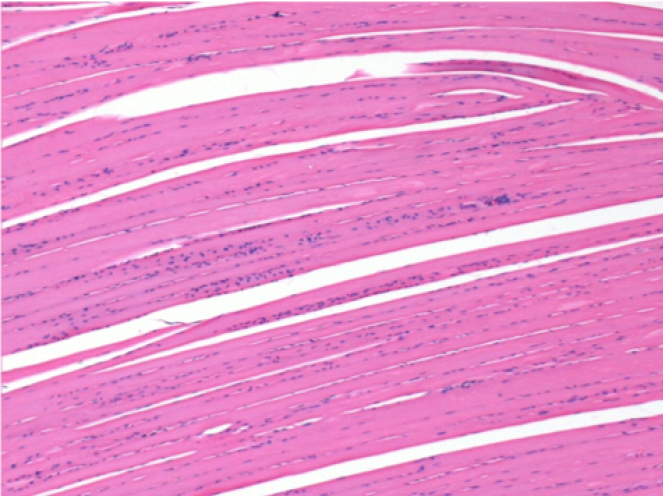

L:Pretibial-No treatment

10 days after Endopeel Injection 0.1ml in the right pretibial muscle.

Here you may see the formation of the vacuoles which are surrounded by lymphocytes. Vacuoles are different from tissue necrosis . The presence of lymphocytes is related to the permeability of the cell membranes.